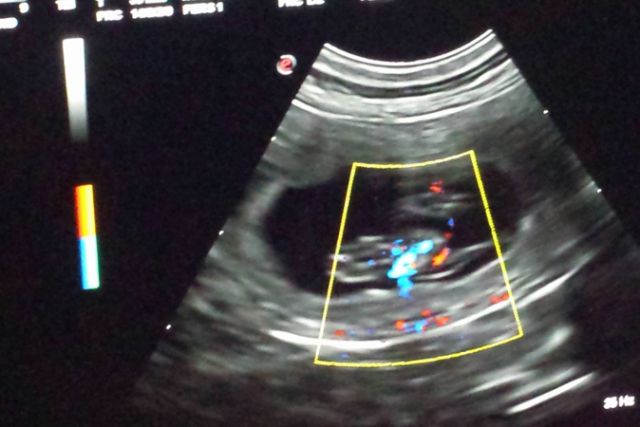

24.02.2017 9. Trächtigkeitswoche – wie viele B-linge das wohl werden? Hedlund hat nochmal sehr gut zugelegt. Ihr gehts prächtig und sie hat mega Appetit.